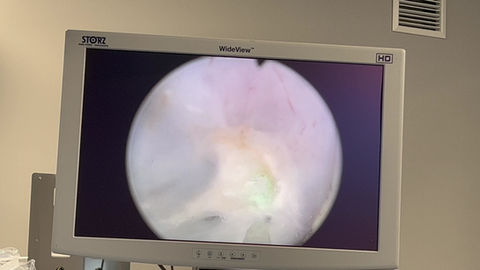

Galería